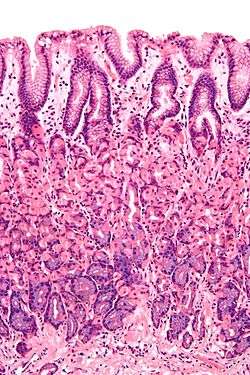

Histology

Like the other parts of the gastrointestinal tract, the stomach walls consist of an outer mucosa, and inner submucosa, muscularis externa, and serosa.

The gastric mucosa of the stomach consists of the epithelium and the lamina propria (composed of loose connective tissue), with a thin layer of smooth muscle called the muscularis mucosae separating it from the submucosa beneath. The submucosa lies under the mucosa and consists of fibrous connective tissue, separating the mucosa from the next layer. Meissner's plexus is in this layer. The muscularis externa lies beneath the submucosa, and is unique from other organs of the gastrointestinal tract, consisting of three layers:

Gastric glands

Different types of cells are found at the different layers of the gastric glands:

| Layer of stomach | Name | Secretion | Region of stomach | Staining |

| Isthmus of gland | Foveolar cells | Mucus gel layer | Fundic, cardiac, pyloric | Clear |

| Body of gland | Parietal (oxyntic) cells | Gastric acid and intrinsic factor | Fundic only | Acidophilic |

| Base of gland | Chief (zymogenic) cells | Pepsinogen and gastric lipase | Fundic only | Basophilic |

| Base of gland | Enteroendocrine (APUD) cells | Hormones gastrin, histamine, endorphins, serotonin, cholecystokinin and somatostatin | Fundic, cardiac, pyloric | – |